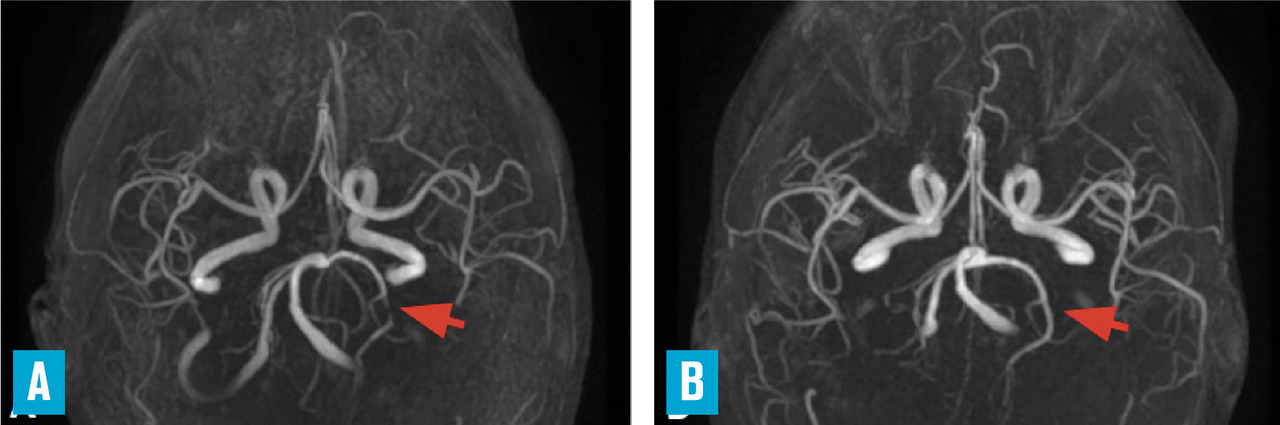

Des présentations radiologiques trompeuses ont été rapportées, telles qu’une large lésion unique d’aspect pseudotumoral, ou encore un aspect de leucoencéphalopathie postérieure. La sensibilité élevée de l’IRM pour déceler des anomalies intracérébrales de petite taille peut être source de difficulté : la présence d’hypersignaux de la substance blanche en séquences T2/FLAIR (leucoaraïose), fréquente dans de nombreuses circonstances, ne doit pas être interprétée trop facilement comme étant un signe de vascularite. Outre les signes parenchymateux sus-décrits, il peut exister en séquence FLAIR (sans injection) une hyperdensité d’artères corticales, témoignant d’un ralentissement circulatoire du fait de sténoses distales. L’exploration parenchymateuse est complétée par une angiographie par résonance magnétique (ARM) intracrânienne pour étudier le polygone de Willis et les premiers centimètres de ses branches de division (

– si la situation paraît stable, une option raisonnable consiste à surveiller le patient et répéter les examens (IRM, angioscanner/ARM, parfois angiographie et ponction lombaire) quelques semaines plus tard : les modifications des anomalies artérielles sur un temps court renforcent la présomption ;

La présence de rétrécissements segmentaires étagés sur les artères intracrâniennes n’est pas spécifique des vascularites cérébrales : outre le syndrome de vasoconstriction cérébrale réversible déjà évoqué (v . tableau ), il peut s’agir d’emboles multiples en voie de recanalisation (origine cardiaque ou artérielle) ou de sténoses athéromateuses. L’atteinte prédominante sur les artères de gros et de moyen calibre, la présence de facteurs de risque vasculaire et des calcifications sur les parois artérielles à la tomodensitométrie cérébrale sont autant d’arguments en faveur d’une athérosclérose intracrânienne, que l’on rencontre en particulier chez les sujets non caucasiens (africains et asiatiques) et chez les diabétiques.2 En cas de difficulté diagnostique, la répétition des explorations artérielles aide à rattacher des anomalies artérielles à une vascularite, en montrant leurs modifications (amélioration ou aggravation) en quelques semaines.